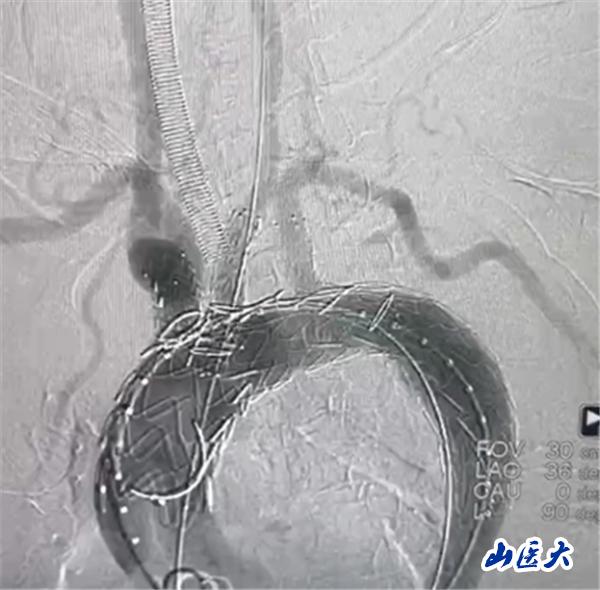

术后效果

首例患者是一位55岁的女性,她患有高血压约2年时间,平时也会规律服用多种降压药,但血压控制始终不尽人意。2023年4月下午,她出现不明原因的头痛,在家拔罐缓解少许便未到医院就医,次日凌晨突感胸闷、胸背疼痛伴有呼吸困难等症状、家人急忙拨打了120,把患者送入医院急诊科进行救治,医生在急诊科行胸腹主动脉CTA时,显示主动脉弓部-降主动脉及腹主动脉壁间血肿,遂收治入医院血管外科,患者入院10天后复查血肿仍未有改善,依然伴有胸背部疼痛等不适,如不进一步处理,可能发展为夹层危及生命,患者及家属经过与医生团队了解沟通,决定进行创伤小、恢复快的介入手术治疗。张玮教授、符伟国教授、董红霖教授及其血管外科团队(闫盛、常文凯、田琴琴)共同商讨手术方案,最终确定使用Zipper™一体式主动脉弓覆膜支架系统,行胸主动脉覆膜支架腔内隔绝术+无名动脉、左颈总动脉、左锁骨下动脉分支重建术为患者进行治疗。董红霖教授及其血管外科团队根据患者术前头颅CT平扫提示双侧侧脑室旁缺血灶,血压控制不稳定,属夹层壁间血肿非典型夹层等风险点,制定了完整的手术方案,术中经股动脉置入Zipper支架主体,经预留导丝超选无名动脉,并确保主体支架对位准确,顺利置入左颈总动脉、左锁骨下动脉支架,重建弓上三分支。手术过程非常顺利。术后观察主动脉及分支覆膜支架定位准确;无内漏;分支支架通畅,动脉供血正常。